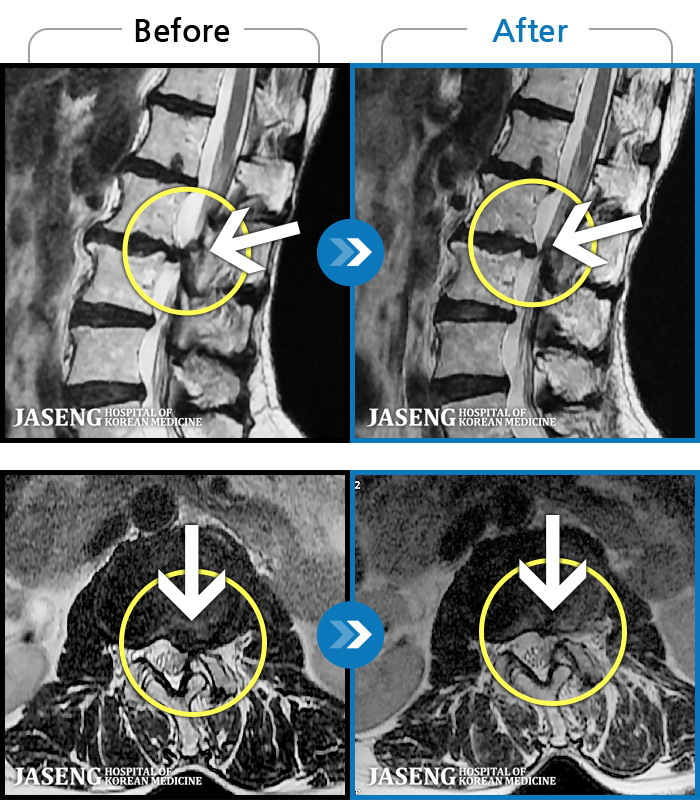

- MRI ġ

MRI ġ

1,299 MRI ũ ʸ Ȯϼ.